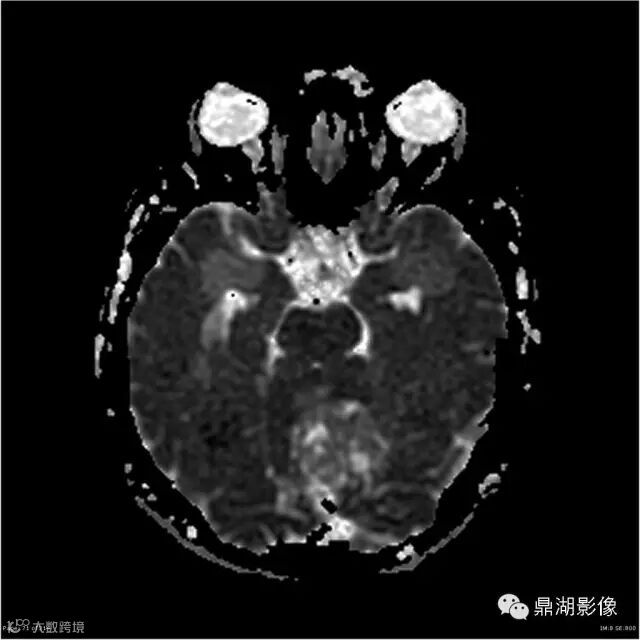

Gradient Echo

影像:可见一个约43 x 36 x 31mm的从小脑蚓部延伸而来的占位,T1WI、T2WI呈高低混杂信号,病灶周边见流空血管影及水肿带,增强病灶明显强化,中心见无明显坏死区,它紧靠左小脑幕上。第四脑室受压变窄,室管膜水肿,可见脑桥及延脑扁桃体进入枕骨大孔。

3、实质型:肿瘤在T1上呈不均匀等或稍低信号,T2上呈不均匀高信号,FLAIR上,肿瘤呈高信号,增强扫描肿瘤呈明显不均匀强化。实质型肿瘤MRI上在瘤内或瘤周可见呈点状、条状或蚯蚓状的血管流空影,这在诊断实质型血管母细胞瘤上具有一定的价值。

本例为一例实质性血管母细胞瘤。实性血管母细胞瘤CT平扫示病灶呈等或高密度,增强后可见明显强化。MRI平扫通常病灶很不均质,T1呈稍低信号为主的较混杂信号,T2呈等、高信号,DWI通常呈低信号或等信号。文献报道,实性血管母细胞瘤较典型的表现为瘤内及瘤周扩张的流空血管影,瘤周中、重度水肿。因此,小脑半球区的单发肿块伴流空血管影,周围大片水肿以及增强后肿块明显强化"形态规则"边界清楚,此时应将实性血管母细胞瘤考虑在内。